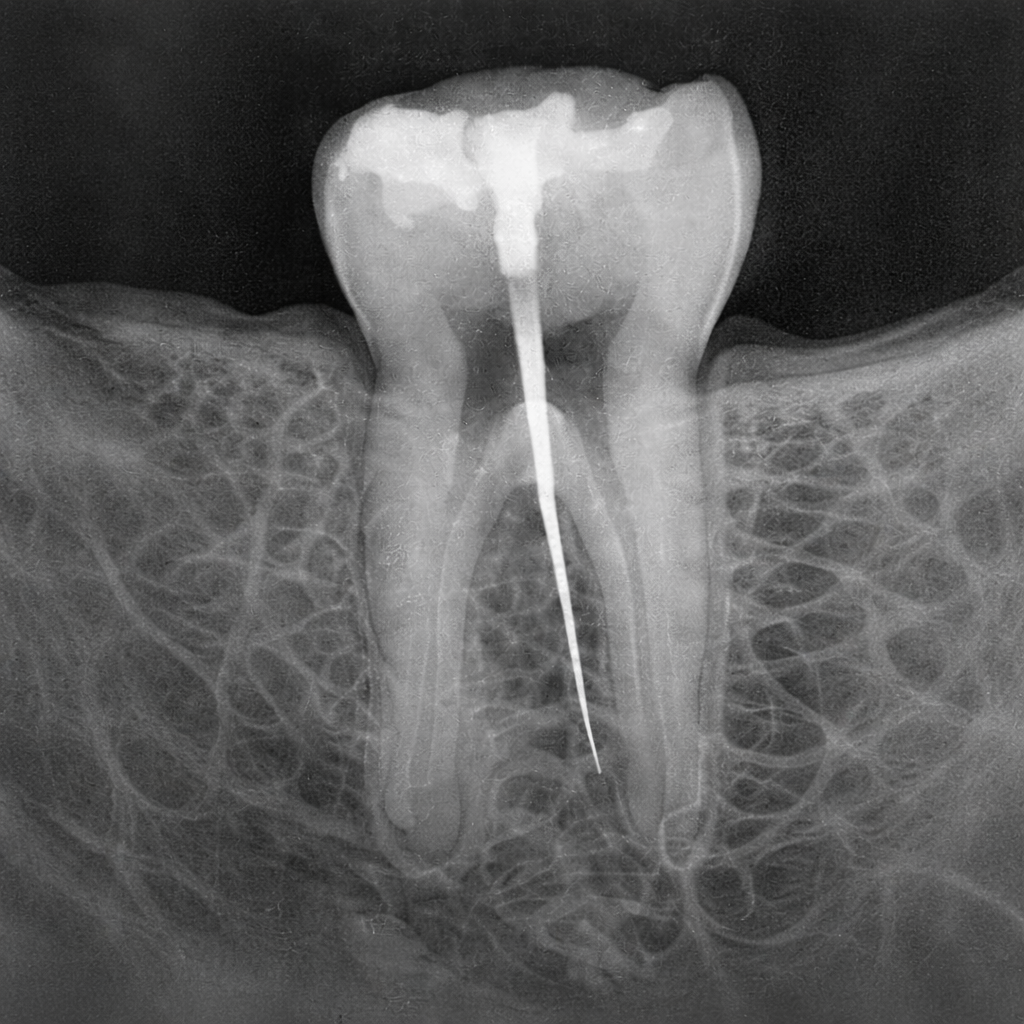

Kanal tedavisi, dişin pulpa dokusunun iltihaplanması veya enfekte olması durumunda uygulanan bir tedavi yöntemidir. Pulpa dokusu; sinirler, damarlar ve bağ dokusundan oluşur ve dişin canlılığını sağlar. Derin çürükler, travmalar veya çatlaklar pulpa hasarına yol açabilir. Tedavi sırasında enfekte doku temizlenir, kök kanalları şekillendirilir ve dezenfekte edilir. Ardından kanallar biyouyumlu dolgu materyalleri ile doldurularak yeniden enfeksiyon oluşması önlenir. Kanal tedavisi, diş çekimini önleyerek doğal dişin ağızda kalmasını sağlar. Modern anestezi ve teknikler sayesinde işlem genellikle konforlu şekilde tamamlanır. Tedavi sonrası dişin dayanıklılığını artırmak için çoğu zaman üst yapı restorasyonu yapılır. Başarılı bir kanal tedavisi ile diş uzun yıllar fonksiyonunu sürdürebilir. Erken müdahale, tedavi başarısını önemli ölçüde artırır.